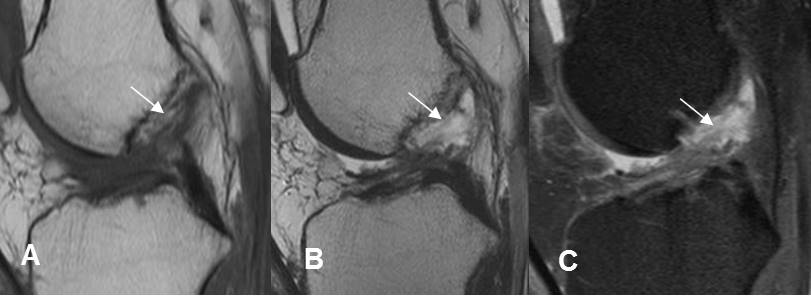

Fig 166. Esguince G III.

A: RM sagital en T1, B: RM sagital en T2 y C: RM sagital en STIR. Ruptura completa del LCA en su origen femoral, con cambios inflamatorios agudos.